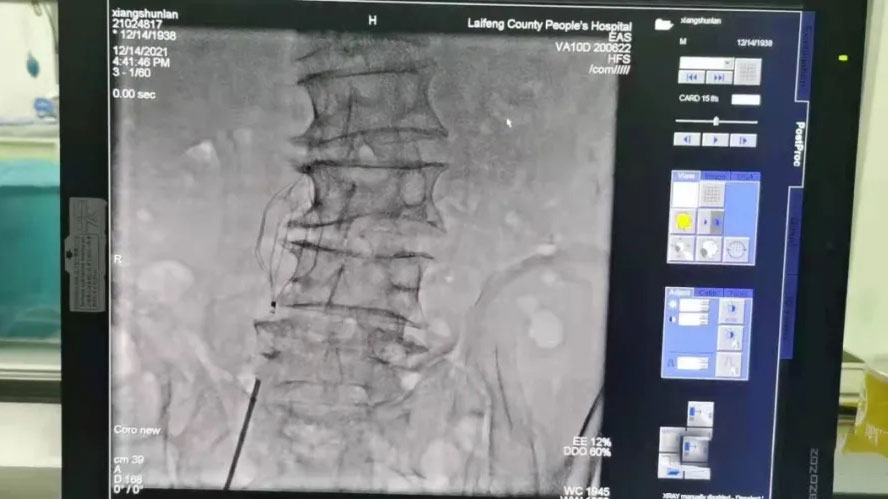

2021年12月14日,来凤县人民医院心血管内科成功为一高龄男性气胸合并下肢静脉血栓患者实施了下腔静脉滤网植入术,填补了该院此项技术的空白。

了解患者病情后,通过与家属沟通后。经过充分、缜密的术前准备,湖北省慧宜医疗集团心血管病中心张宏伟教授联合来凤县人民医院张承中副院长兼心血管内科主任为患者行下腔静脉滤网植入术,在最短的时间内成功放置了下腔静脉滤器,从而避免了急性肺栓塞的可能,为后续治疗赢得了宝贵的时间。“下腔静脉滤网置入术是将选定的金属滤网通过股静脉置入下腔静脉内,形成对下肢静脉栓塞的拦截,在下腔静脉中撑开了一把“保护伞”,可有效预防患者治疗过程中血栓脱落引起的致命性栓塞。适用于:有下肢深静脉血栓形成的高危患者,如颅脑损伤、骨折,慢性肺动脉高压伴高凝血状态的患者,肢体长期制动、重症监护室的患者,高龄、长期卧床的患者。”